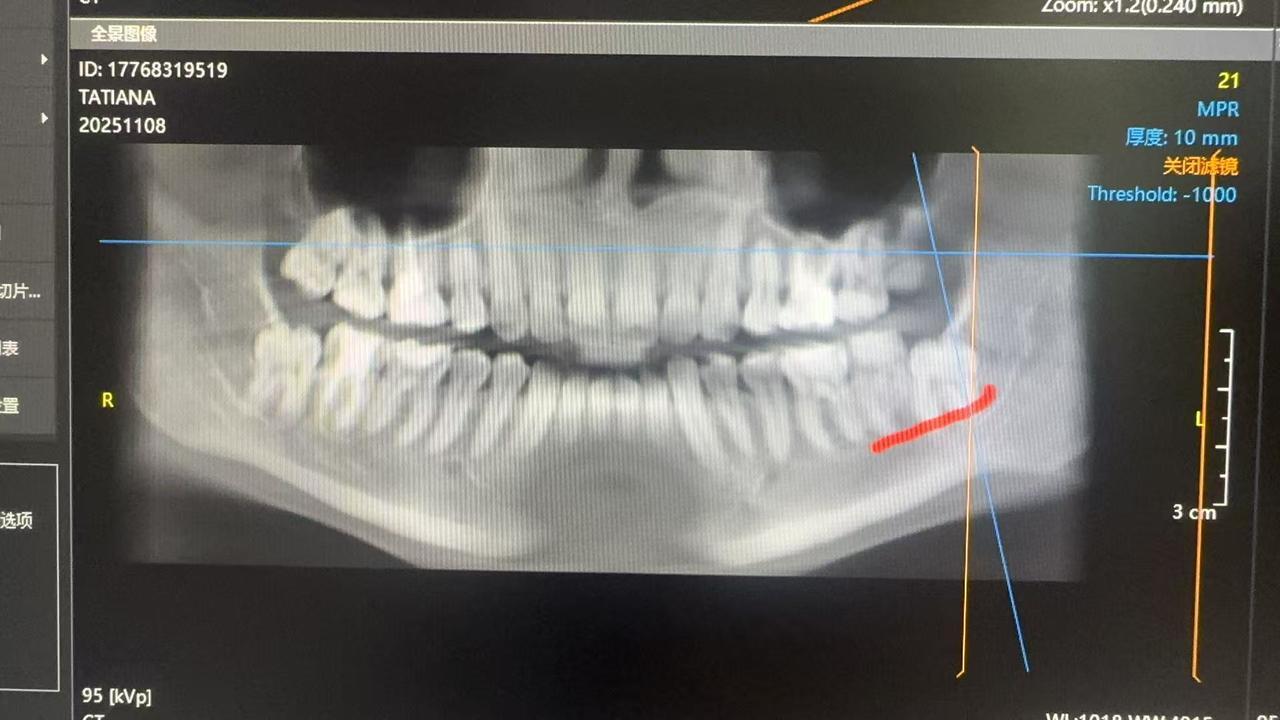

Ситуация:

Нижние зубы затрагивают лицевой нерв, говорят нельзя удалять, но они давят и начинают искривлять остальные зубы, над ними еще челюстная кость, наверх не могут прорасти. Пока думаю несколько вариантов, либо удалить соседние, либо отпилить часть кости, установить винты и ждать 3-6 месяцев когда вырастут, потом удалять, когда отойдут от нервов или найти челюстно-лицевого хирурга, но 100% гарантии, что нервы не затронут не дают. Поэтому я все еще в поисках специалиста и более безопасного решения 😅

КТ ПРИКРЕПЛЯЮ